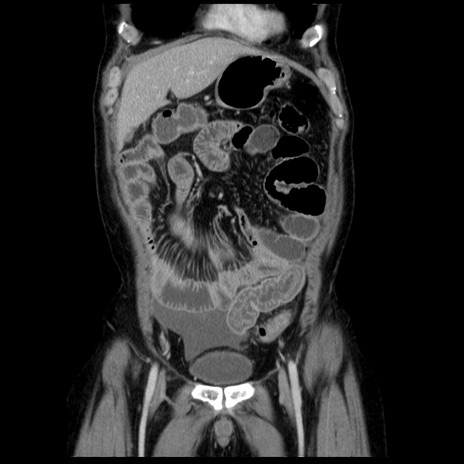

横断像

【症例】40歳代男性

【現病歴】2日前から胃痛あり。徐々に周期的な激痛に変化した。本日になっても激痛があるため受診。

【身体所見】意識清明、BT 38-39℃台あり、腹部:膨満、やや硬、右下腹部に圧痛あり。

【データ】WBC 8500、CRP 23.26